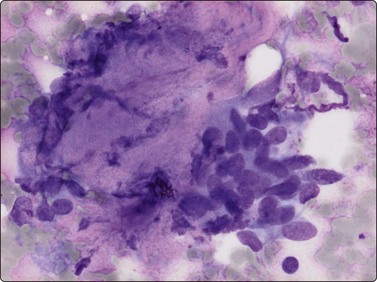

Proliferative myositis and fasciitis are less frequent pseudosarcomatous processes but are important with regard to the rapid growth (common to all these lesions) and their occurrence in children. Their cytomorphology is similar to that of nodular fasciitis although the myxoid matrix is less prominent and the ganglion cell-like cells are often numerous with very prominent nucleoli (Fig. 15.3). In proliferative myositis regenerating multinucleated muscle fibers are commonly present (Fig. 15.4). An important clinical sign is that these lesions, especially nodular fasciitis, can disappear spontaneously or diminish substantially in size within 3–4 weeks after needling.15,16 Another lesion which cytologically demonstrates prominent reactive cellular changes is pseudomalignant myositis ossificans (PMO). PMO is a rapidly growing lesion (intramuscular or subcutaneous), smears showing a mixture of proliferating fibroblasts/myofibroblasts, osteoblasts with prominent reactive changes and multinucleated giant cells of osteoclastic type (Fig. 15.5). In PMO an ossification in a zonal pattern is a typical find within 3–4 weeks and, according to our experience, spontaneous resolution is common. The cytomorphology in our series of five cases17 is similar to that described by Dodd et al.13

image

Fig. 15.3 Proliferative fasciitis

Ganglion cell-like cells are often numerous with very prominent nucleoli (H&E, HP).

Fig. 15.4 Proliferative myositis

Regenerating muscle fibers are commonly present (MGG, HP).